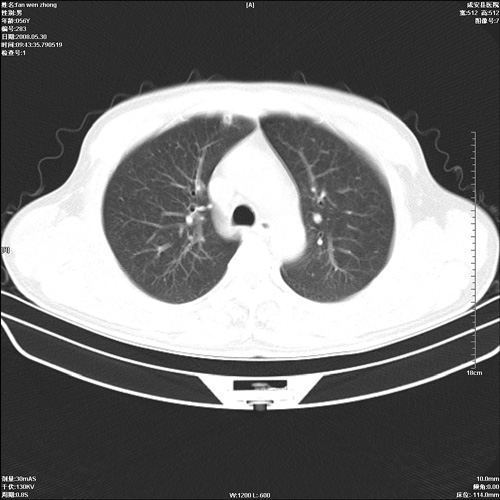

病人 男 56岁 一周前高热,体温达39-40度,经抗炎治疗后,体温渐降,达37,5-38度,轻微咳嗽,胸部不适 查白细胞为1.3万 行ct检查,请分析。

双肺内可见多发结节状病灶,并见小空洞,病人高热,白血球增高,应该是典型的迁徙性肺脓肿(多为金黄色葡萄球菌感染)。查一下口腔等其它部位有无感染灶。

双肺内可见多发结节状病灶,并见小空洞,病人高热,白血球增高,应该是典型的迁徙性肺脓肿(多为金黄色葡萄球菌感染)。建议治疗后复查.